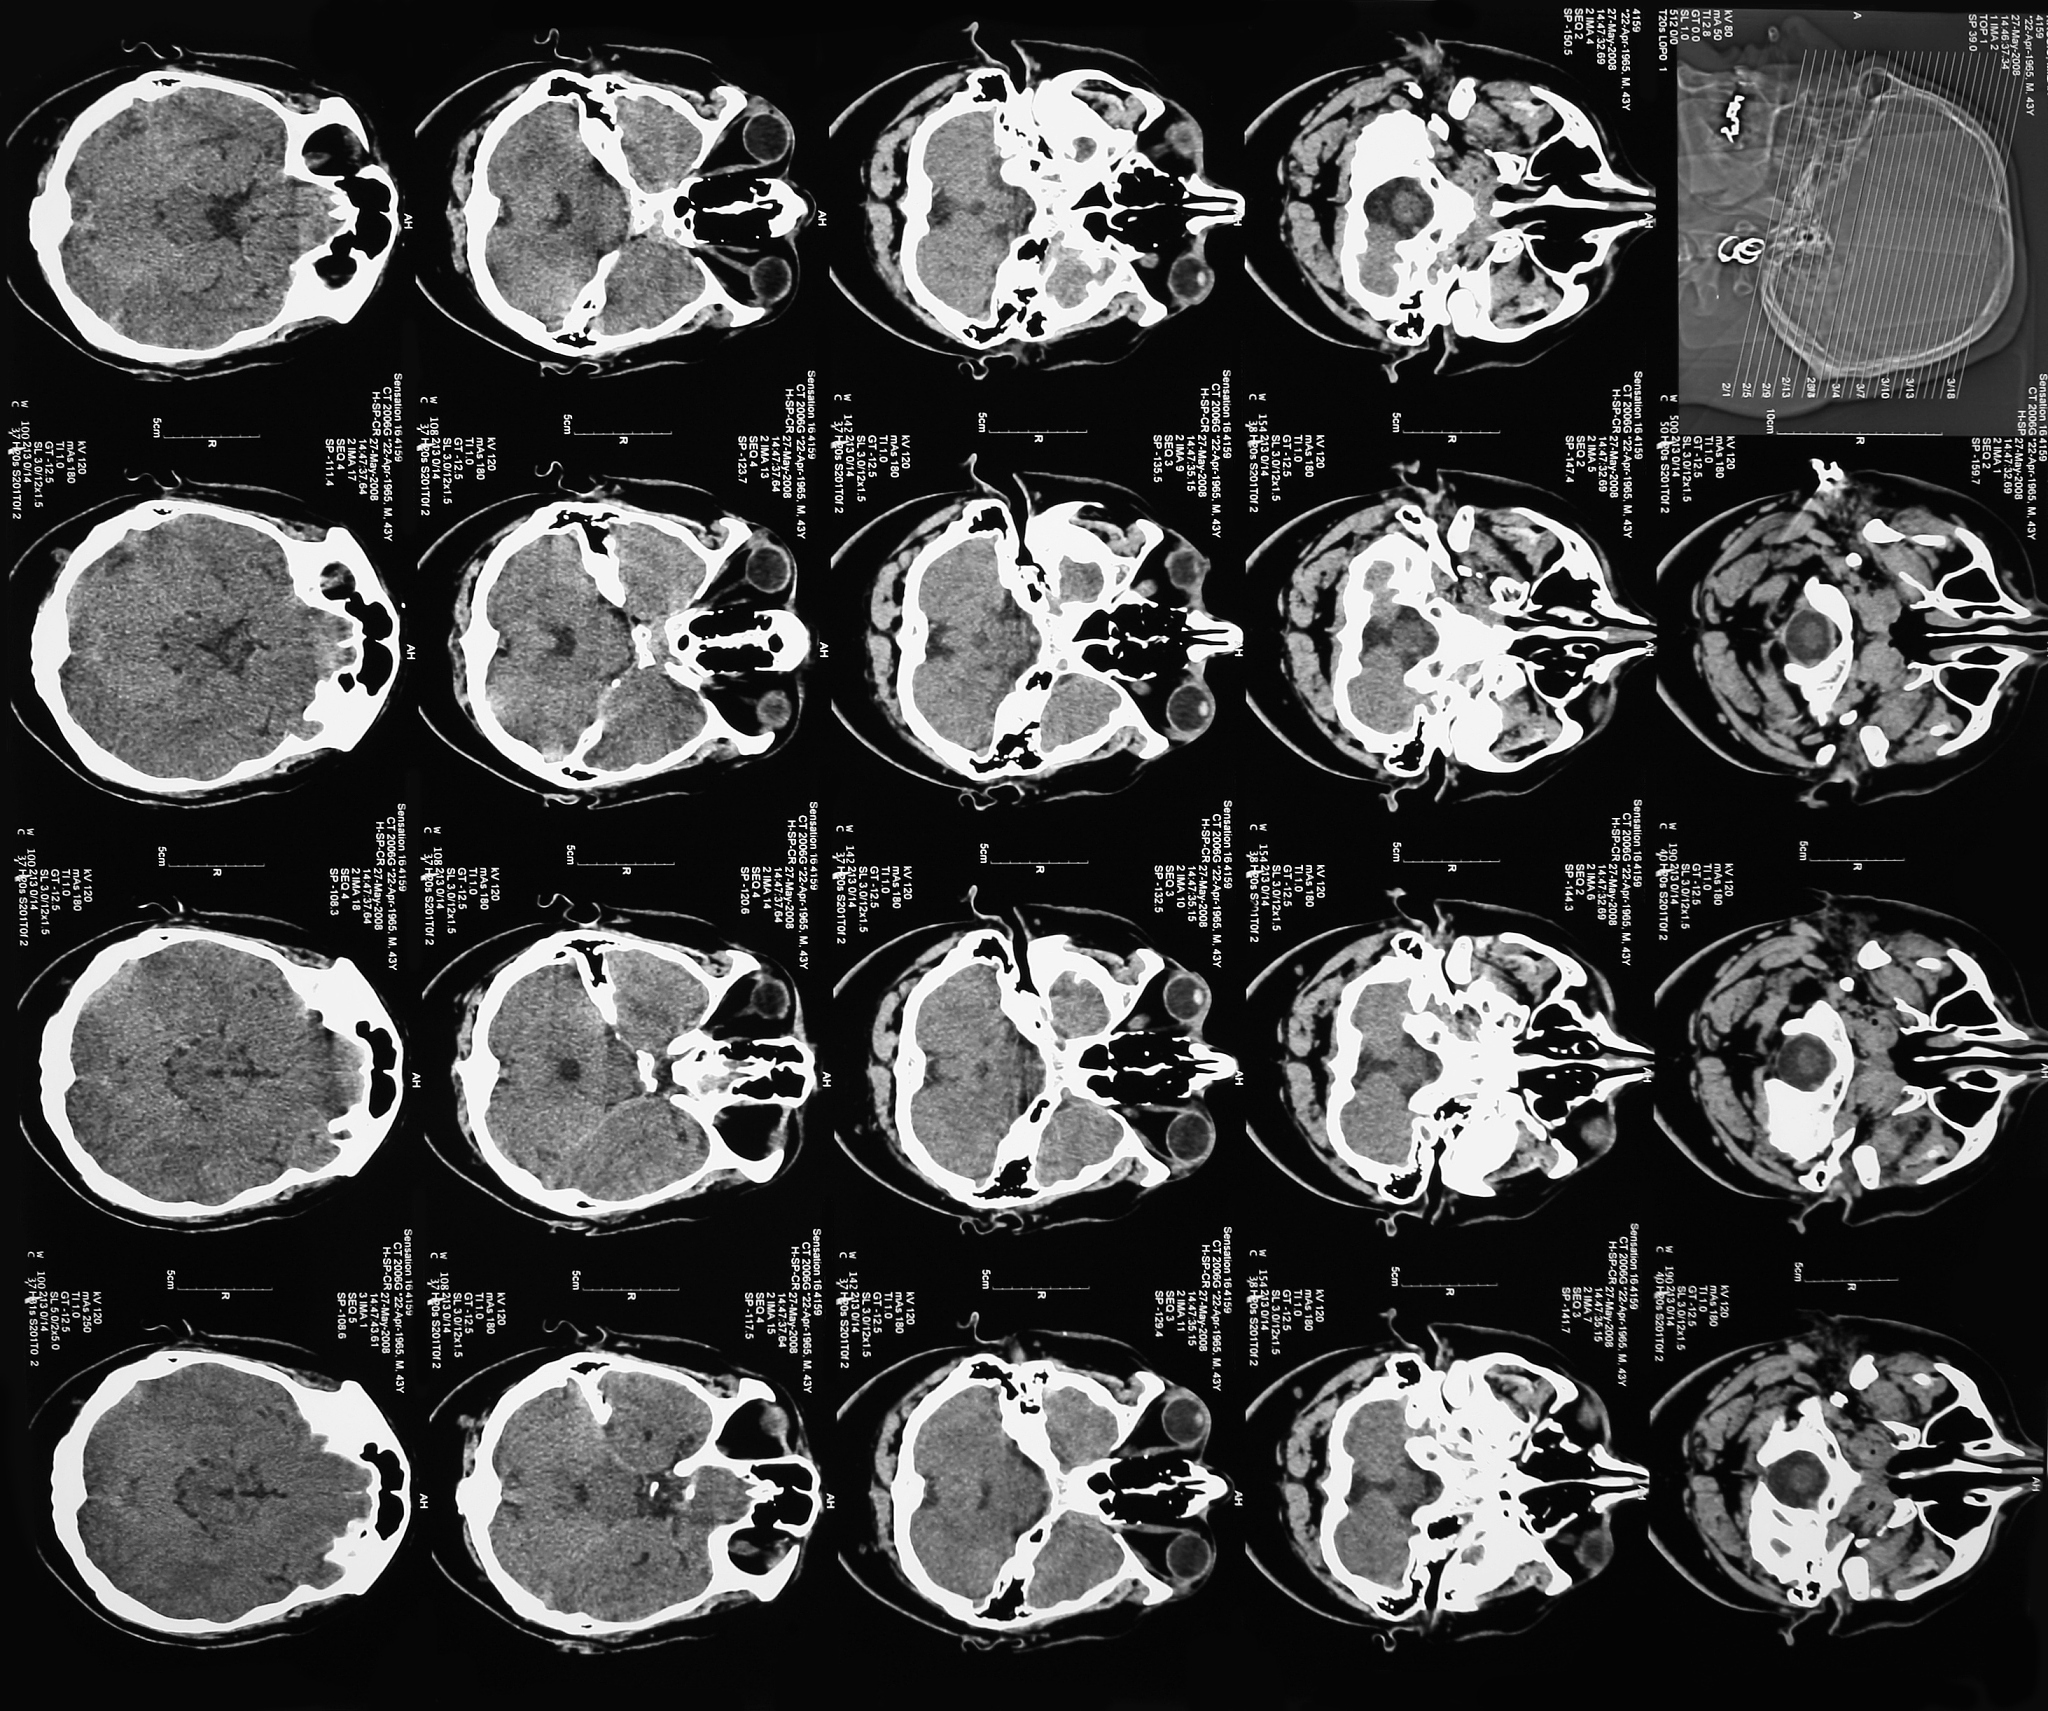

腺泡状软组织肉瘤的CT和MR诊断相对难度较大。虽然CT可以提供高分辨率的图像,但该病变的CT表现非特异性,常常呈现为软组织肿块,难以与其他肿瘤区分。MR可以提供更为详细的组织学信息,但该病变的MR表现也缺乏特异性,常常呈现为均匀或不均匀的低信号或等混杂信号病变。因此,对于腺泡状软组织肉瘤的确诊需要结合临床表现、影像学特征以及组织病理学特征综合判断。